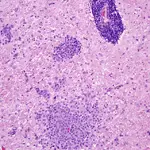

• GME is characterized by a unique angiocentric granulomatous encephalitis consisting of a perivascular accumulation of macrophages often intermixed with lymphocytes and plasma cells. Three major patterns of histologic lesion distribution in the brain and spinal cord have been described for GME:

The disseminated form, in which the most intense lesions occur in the upper cervical spinal cord, brainstem, and midbrain, often with less severe extension involving white matter of the rostral cerebrum (Figure 3).

Figure 3

GME. Disseminated form of GME with an angiocentric expansive infiltration of macrophages sometimes mixed with lymphocytes and a few plasma cells. (_H&E stain, 130×).

A disseminated form with angiocentric expansion forming multiple coalescing mass lesions of similar distribution.

A focal form, in which single discrete mass lesions occur in either the spinal cord, brainstem, midbrain, thalamus, optic nerves, or cerebral hemispheres, without dissemination. It remains contentious whether this form is a neoplastic rather than an immunoproliferative process.